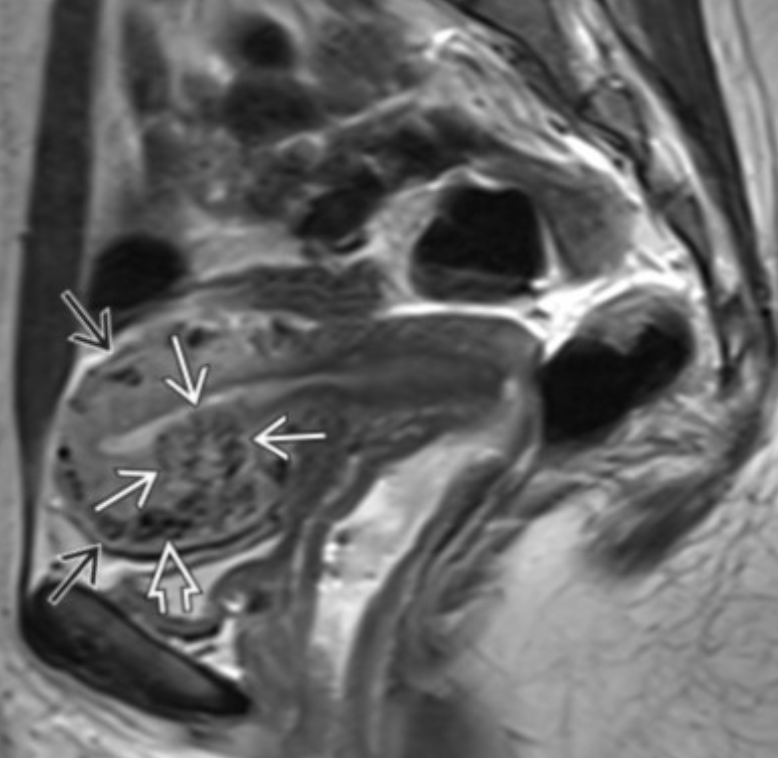

• Specific to MR

• Thick junctional zone with indistinct margins

• T2 bright foci in endometrial & myometrium (sometimes T1 bright too)

• This is how you differentiate it from a fibroid